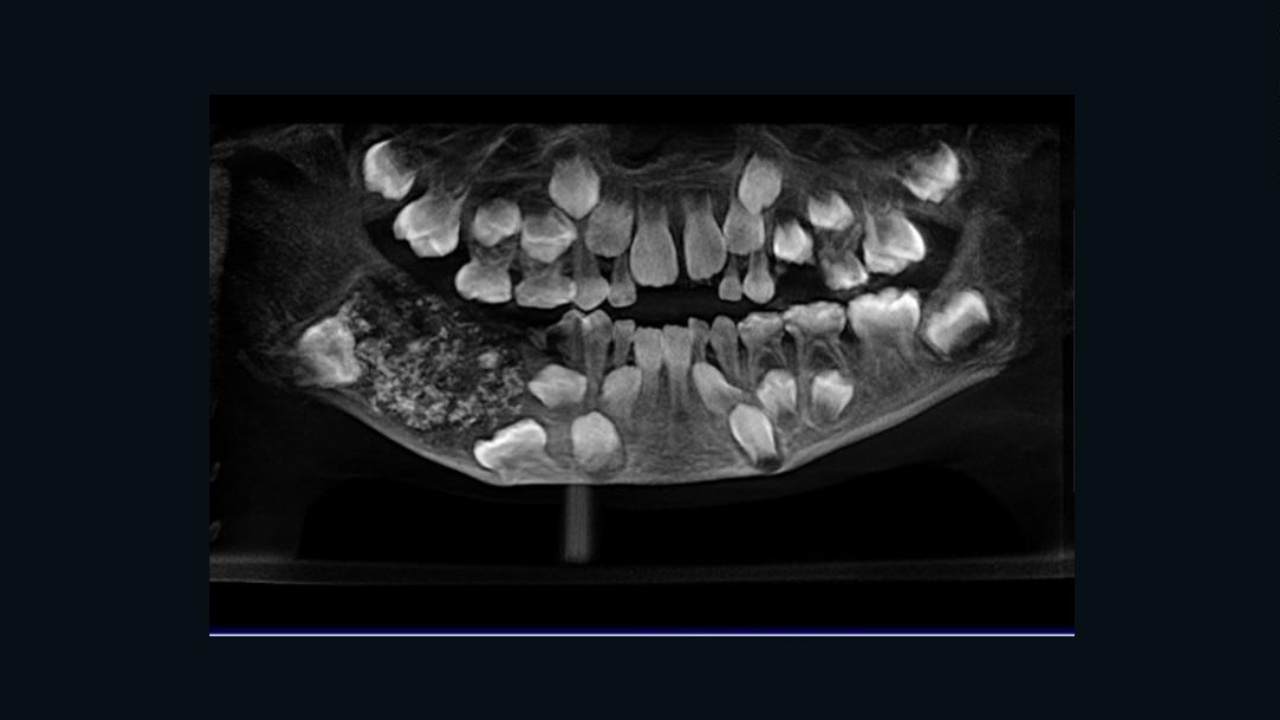

สำนักข่าว ซีเอ็นเอ็น รายงานเมื่อ 1 ส.ค. 2562 ว่า เด็กชายคนนี้ถูกนำตัวเข้ารักษาที่โรงพยาบาลในเมืองเจนไนเมื่อเดือนกรกฎาคมที่ผ่านมา หลังจากมีอาการบวมและปวดใกล้ฟันกรามด้านขวาล่าง เมื่อแพทย์ตรวจด้วยการสแกนและเอ็กซ์เรย์ก็พบส่วนที่คล้ายถุง ซึ่งภายในเต็มไปด้วยฟันที่ผิดปกติ

ดร.ประธิพา รามณี หัวหน้าแผนกพยาธิวิทยาช่องปากและใบหน้าของวิทยาลัยและโรงพยาบาลทันตกรรม สวีธา บอกกับซีเอ็นเอ็นว่า แพทย์ต้องใช้เวลาตรวจสอบถุงและฟันดังกล่าว ก่อนจะตัดสินใจผ่าตัด ซึ่งศัลยแพทย์ 2 คนนำถุงออกจากปากของเด็กได้สำเร็จ และพบฟันหลายร้อยซี่

“มีฟันทั้งหมด 526 ซี่ ขนาดตั้งแต่ 1 มม.ถึง 15 มม. แม้แต่ซี่ที่เล็กที่สุดก็มี ครอบฟัน, ราก และเคลือบฟันที่บ่งชี้ว่ามันคือฟัน” ดร.รามณีกล่าว โดยเด็กสามารถออกจากโรงพยาบาลหลังผ่าตัด 3 วัน และคาดว่าจะหายเป็นปกติ